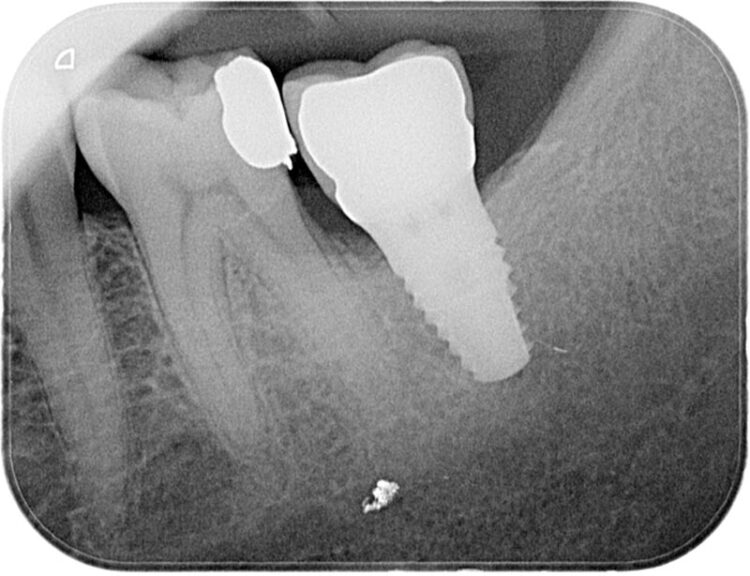

Following three months of healing, a CBCT scan was taken to assess bone dimensions and proximity of nearby anatomical landmarks, namely the inferior dental nerve and the lingual undercut of the mandible.

3-D radiographic examination showed sufficient bone available for the placement of a 5.8mm x 9mm BioHorizons Camlog tapered tissue level implant. Surgical placement of this implant involved a two-sided flap and there was no need for hard or soft tissue augmentation. The implant was placed with excellent primary stability and therefore a single-staged approach was followed with a healing abutment being placed at implant placement.